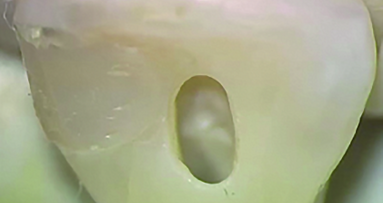

When testing the mineral layers, the researchers observed that the peptide bonded well to the dentine surface by attracting calcium and phosphate ions, forming a hydroxyapatite mineral layer. The resulting layer not only occluded the dentinal tubules but also promoted dentine repair by remineralising the surface, resulting in a well-integrated and long-lasting layer.

The study, titled “Biomimetic dentin repair: Amelogenin-derived peptide guides occlusion and peritubular mineralization of human teeth”, was published on 13 March 2023 in ACS Biomaterials Science and Engineering.